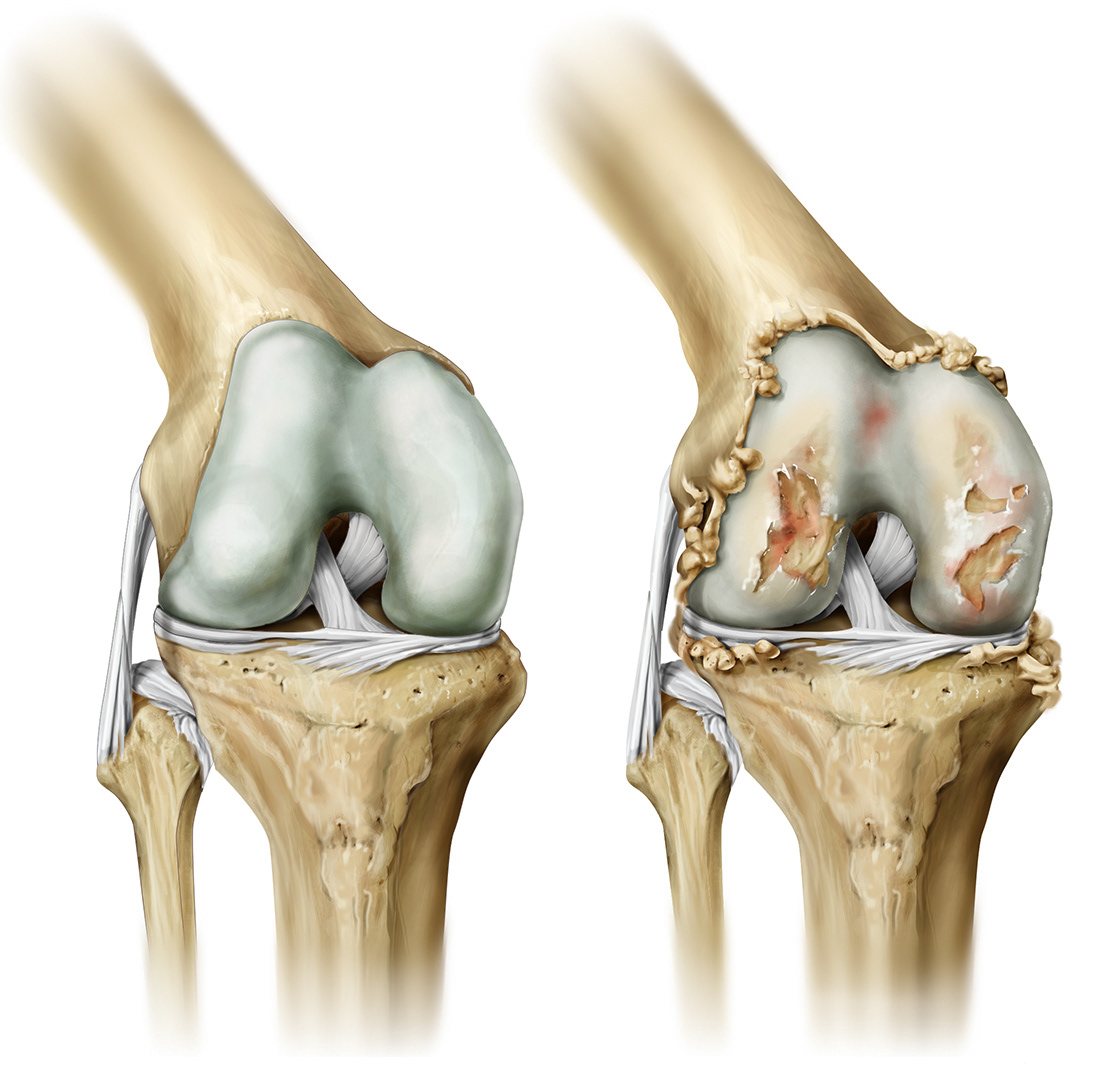

Entenda os sintomas da artrose no joelho e descubra como o tratamento ortopédico e a fisioterapia podem aliviar dores e melhorar a mobilidade.

O que é a artrose no joelho?

A artrose é uma doença degenerativa que causa o desgaste da cartilagem das articulações. No joelho, ela provoca dor, inchaço e dificuldade para realizar atividades simples como andar ou subir escadas.